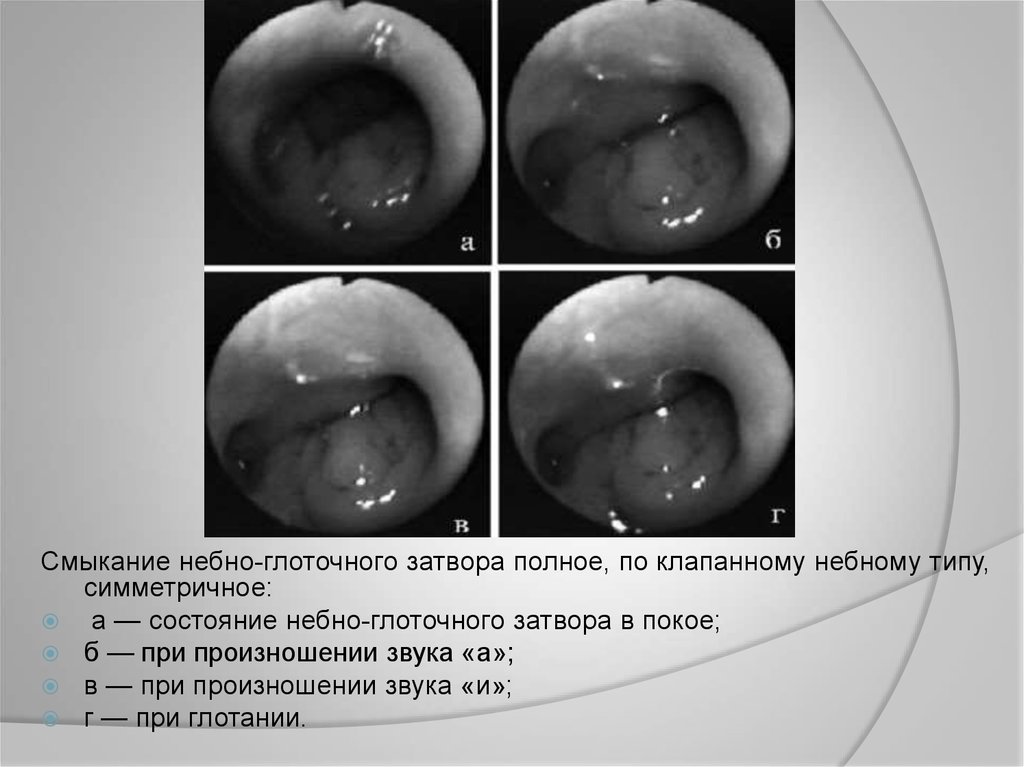

Смыкание небно-глоточного затвора полное, по клапанному небному типу,

симметричное:

а — состояние небно-глоточного затвора в покое;

б — при произношении звука «а»;

в — при произношении звука «и»;

г — при глотании.